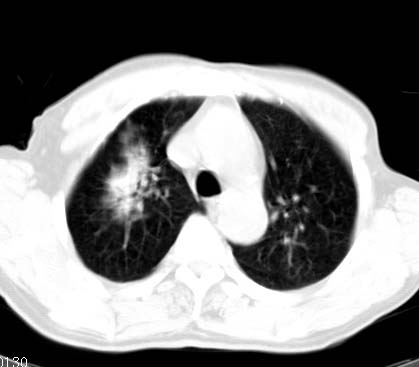

标题: CT14027:男性病人 71岁 咳嗽咳痰数周. [打印本页]

标题: CT14027:男性病人 71岁 咳嗽咳痰数周.

男性病人 71岁 咳嗽咳痰数周.诊断结核应该有保障吧!

右上肺结核,请结合痰检除外活动期;右上叶支气管官腔狭窄建议支气管镜或抗僗后随诊除外堵塞性改变。

支持双上肺继发性肺结核。